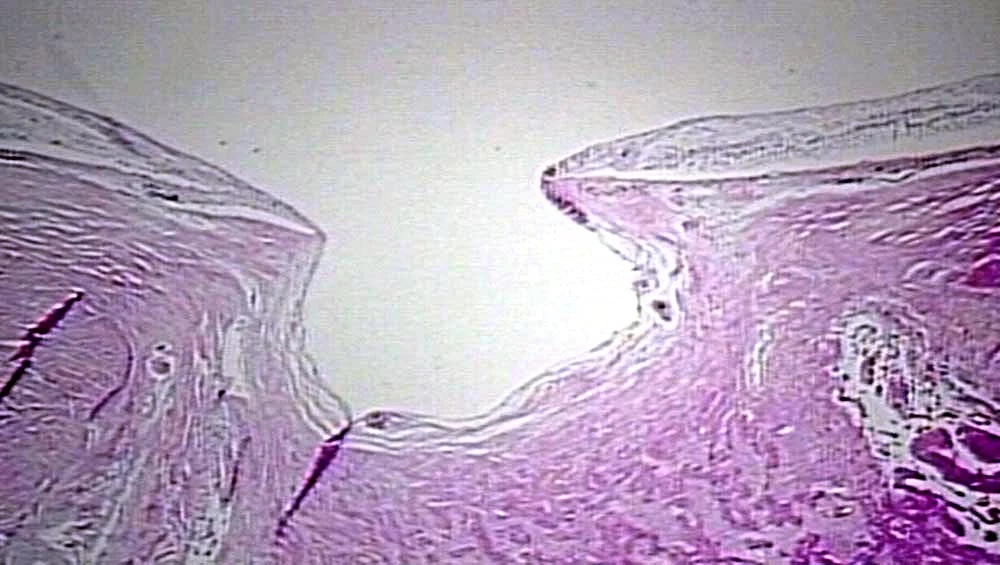

From entokey.com

The Optic Disc Ento Key Optic Nerve Hypoplasia Eyewiki optic nerve hypoplasia is the most common congenital optic nerve anomaly. optic nerve coloboma spectrum comprises a spectrum of diseases with overlapping characteristics (cavitation of the optic disc), but overall different clinical. It is a unilateral or bilateral malformation of the optic nerve with a wid. foveal hypoplasia is an ocular abnormality in which the foveal pit. Optic Nerve Hypoplasia Eyewiki.